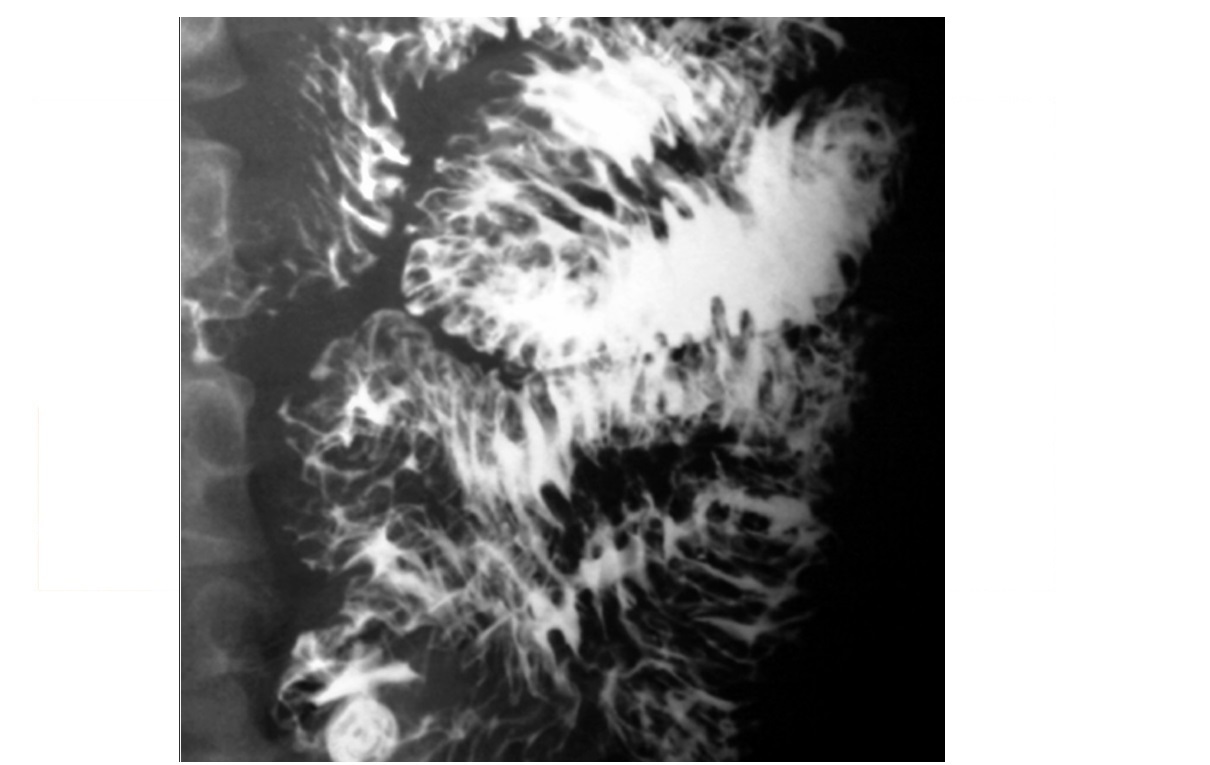

Menetriers disease

SPARES the antrum

Hyperplastic gastropathy/ protein-losing gastropathy

Grossly thickened, lobulated folds in gastric fundus and body with poor barium coating. low albumin

CT - Massive thickening of mucosa and submucosa, giant, mass-like, tortuous folds resemble cerebral convolutions

DDx

Gastritis - thickened lobulated folds favour antrum

ZES - Multiple ulcers, pancreatic tumor (gastrinoma)